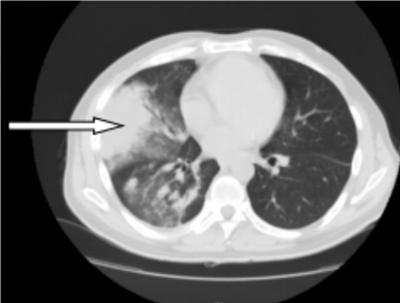

41岁的彭先生,2022年3月份出现咳嗽咳痰,多家立博体育 治疗效果不佳,外院查胸部CT提示肺部占位及大量胸水,且外周血白细胞明显升高及颈部多发的淋巴结肿大。4月初疑诊结核收入立博体育 结核科,入院后发现浅表淋巴结进行性增大,经血液科会诊,考虑淋巴瘤并骨髓侵犯。患者转入血液内科后,行骨髓涂片提示有77%肿瘤细胞,同时请耳鼻喉科行颈部淋巴结切除病检,最终确诊为低级别滤泡性淋巴瘤并肺部、骨髓侵犯(IV期,EZH2基因突变阴性)。4月27日根据最新的滤泡性淋巴瘤诊治指南(NCCN指南及CSCO指南),选用GB方案(奥妥珠单抗联合苯达莫司汀)化疗。第一周期化疗后,彭先生状态良好。5月26日复查肺部CT,肺部占位、胸水及淋巴结明显缩小。咳嗽及气促也完全消失。目前,患者仍在血液内科接受后续治疗。

图一:4月10日化疗前肺部CT,箭头所指肺部为淋巴瘤浸润引起的肺实变(胸水已引流)